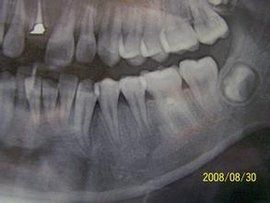

2.1.3 暫時充填窩洞,每3個月複診1次,拍攝X線片,觀察1~2年。

3.3 治療過程中應注意的事項 (1)徹底清除根管內感染物質,消除根尖周圍炎症。因為控制感染才能使牙乳頭和上皮根鞘的活力得以恢復,促使牙根的繼續發育。因此,徹底清除根管內感染物質是促使根尖形成的重要因素。(2)在使用根管器械清除感染牙髓前,應先依據X線片測量其工作長度,避免將感染物質推出根尖或刺傷根尖部組織。年輕恆牙的牙髓和根尖周組織發生病變後,牙根的繼續發育取決於尖周組織中牙乳頭和上皮根鞘功能的恢復。如果工作長度測量值較實際值大時,根管器械超出根尖,損傷牙乳頭和上皮根鞘,將導致誘導失敗。